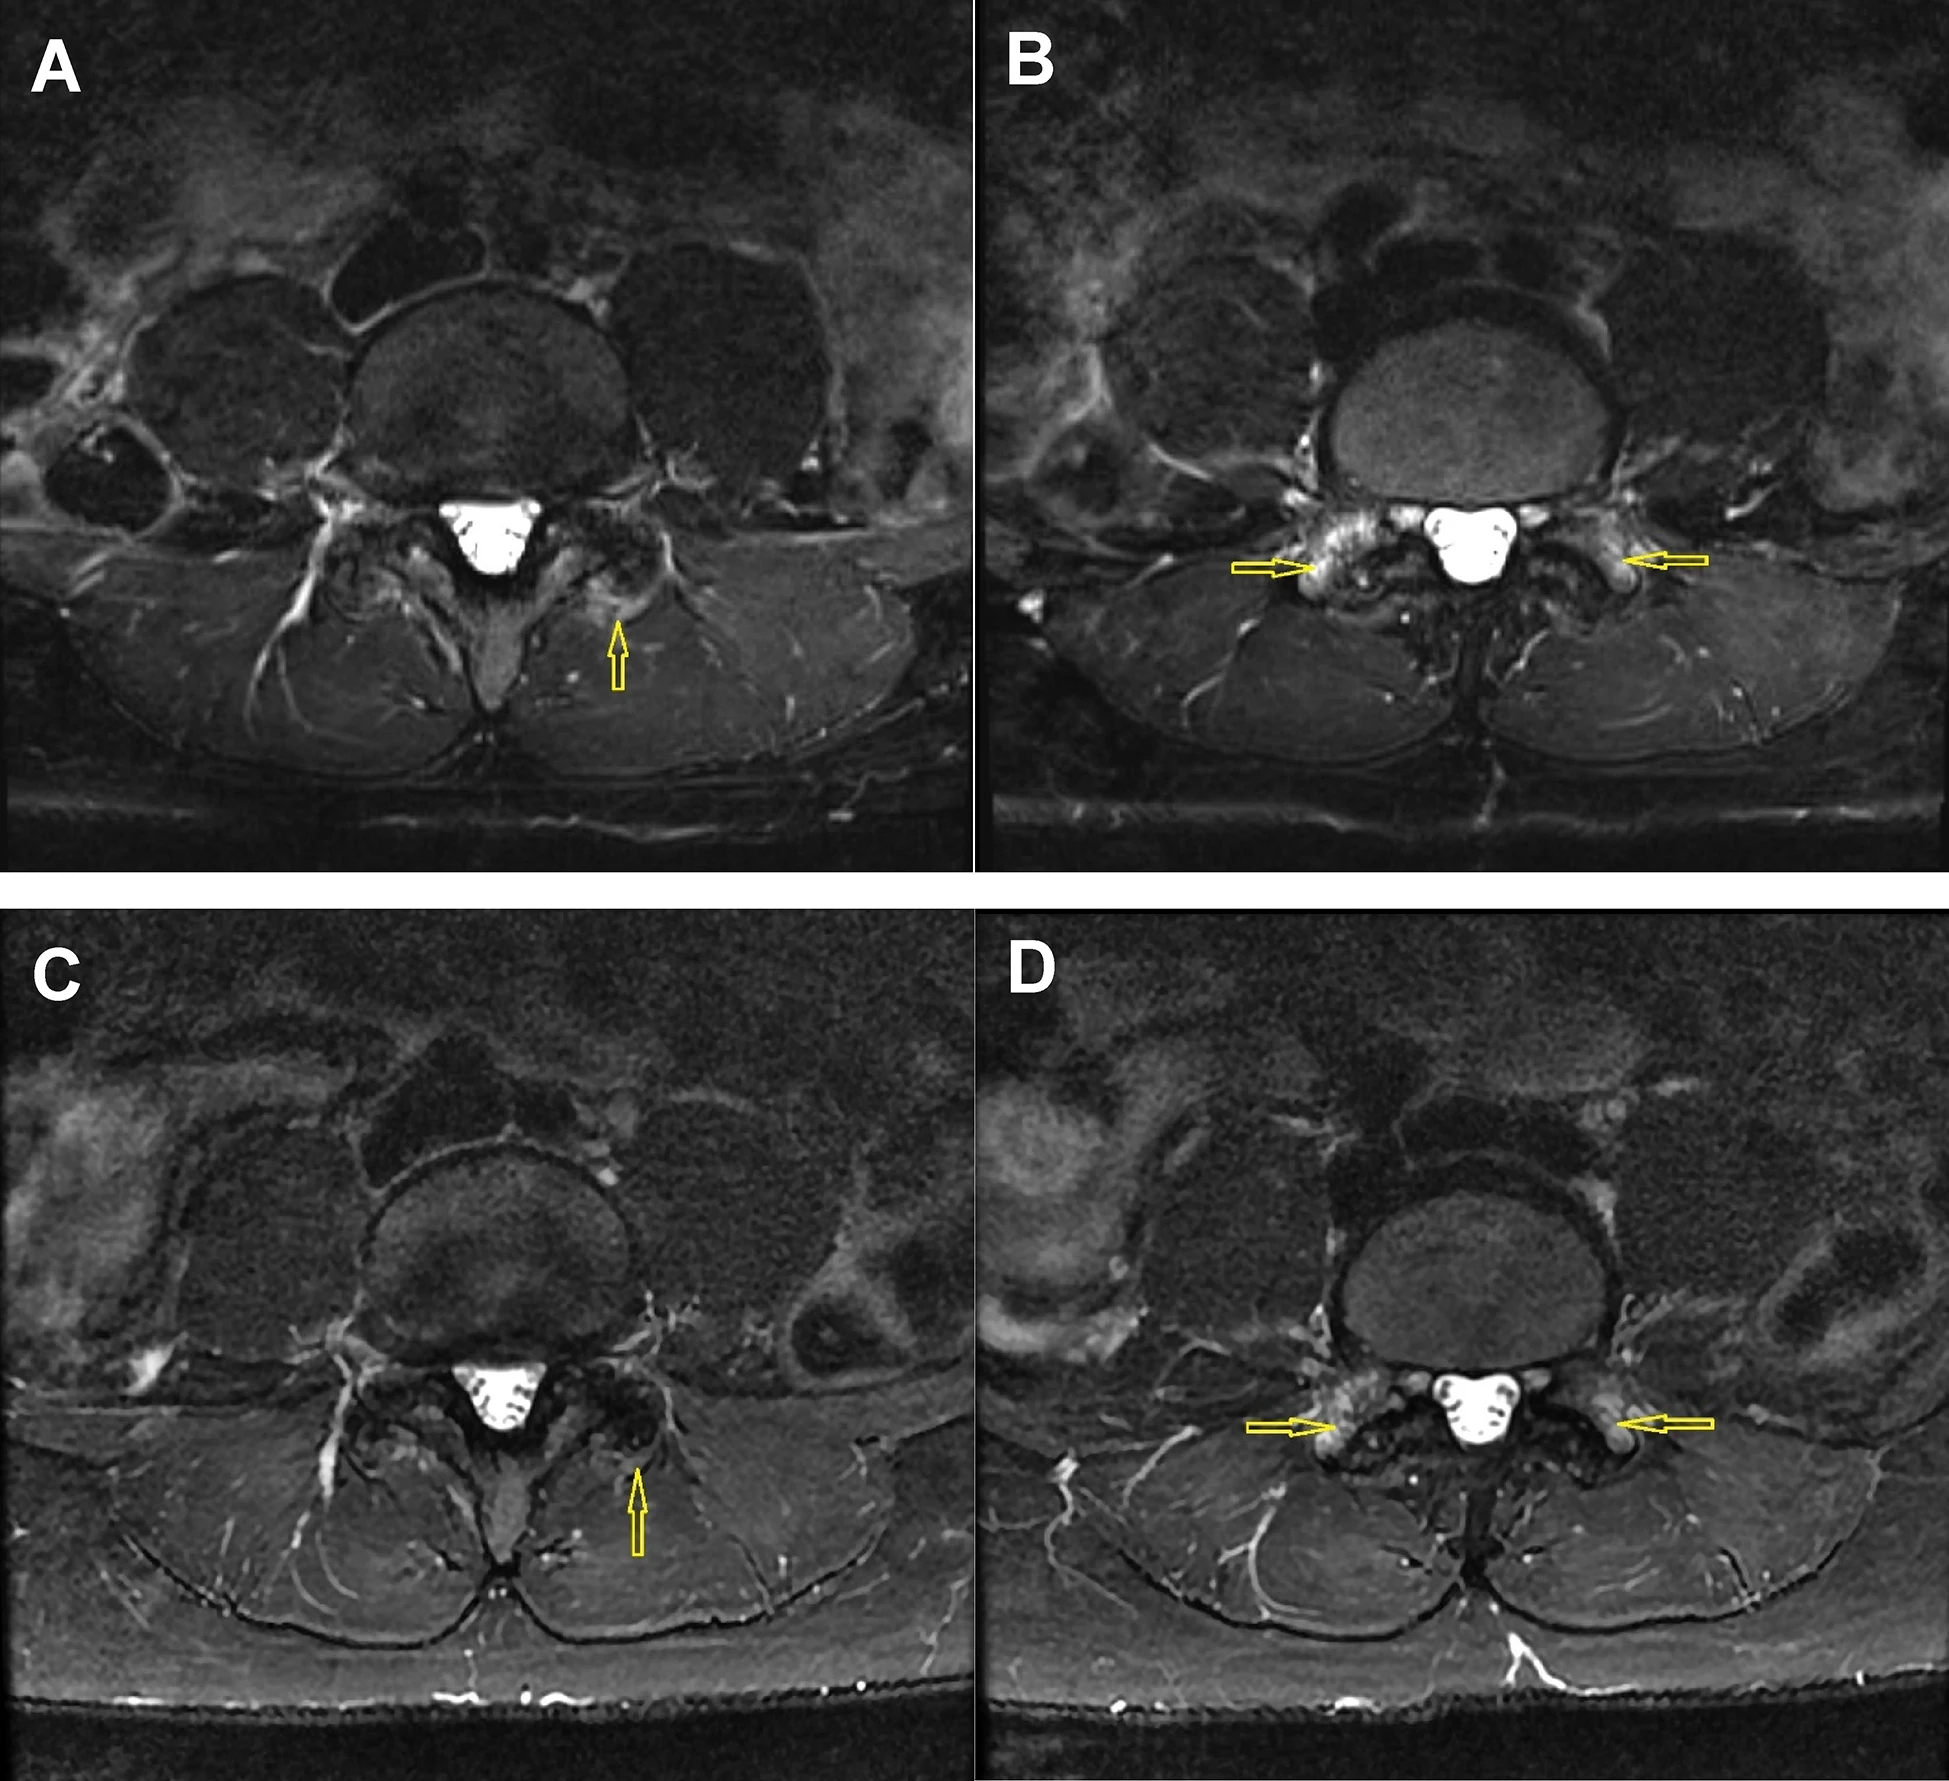

图2:图A和B为骨髓间充质干细胞(BM-MSC)注射前,图C和D为注射后24个月的L4-L5小关节脂肪抑制T2加权轴位Dixon图像。治疗前图像A显示左侧小关节周长50%以上出现水肿;图像B显示双侧L5上关节突广泛反应性骨髓水肿(3级滑膜炎)。治疗后24个月,图像C显示关节囊水肿明显减轻,关节周长50%以下;图像D显示双侧骨髓水肿略有减轻(2级滑膜炎)。